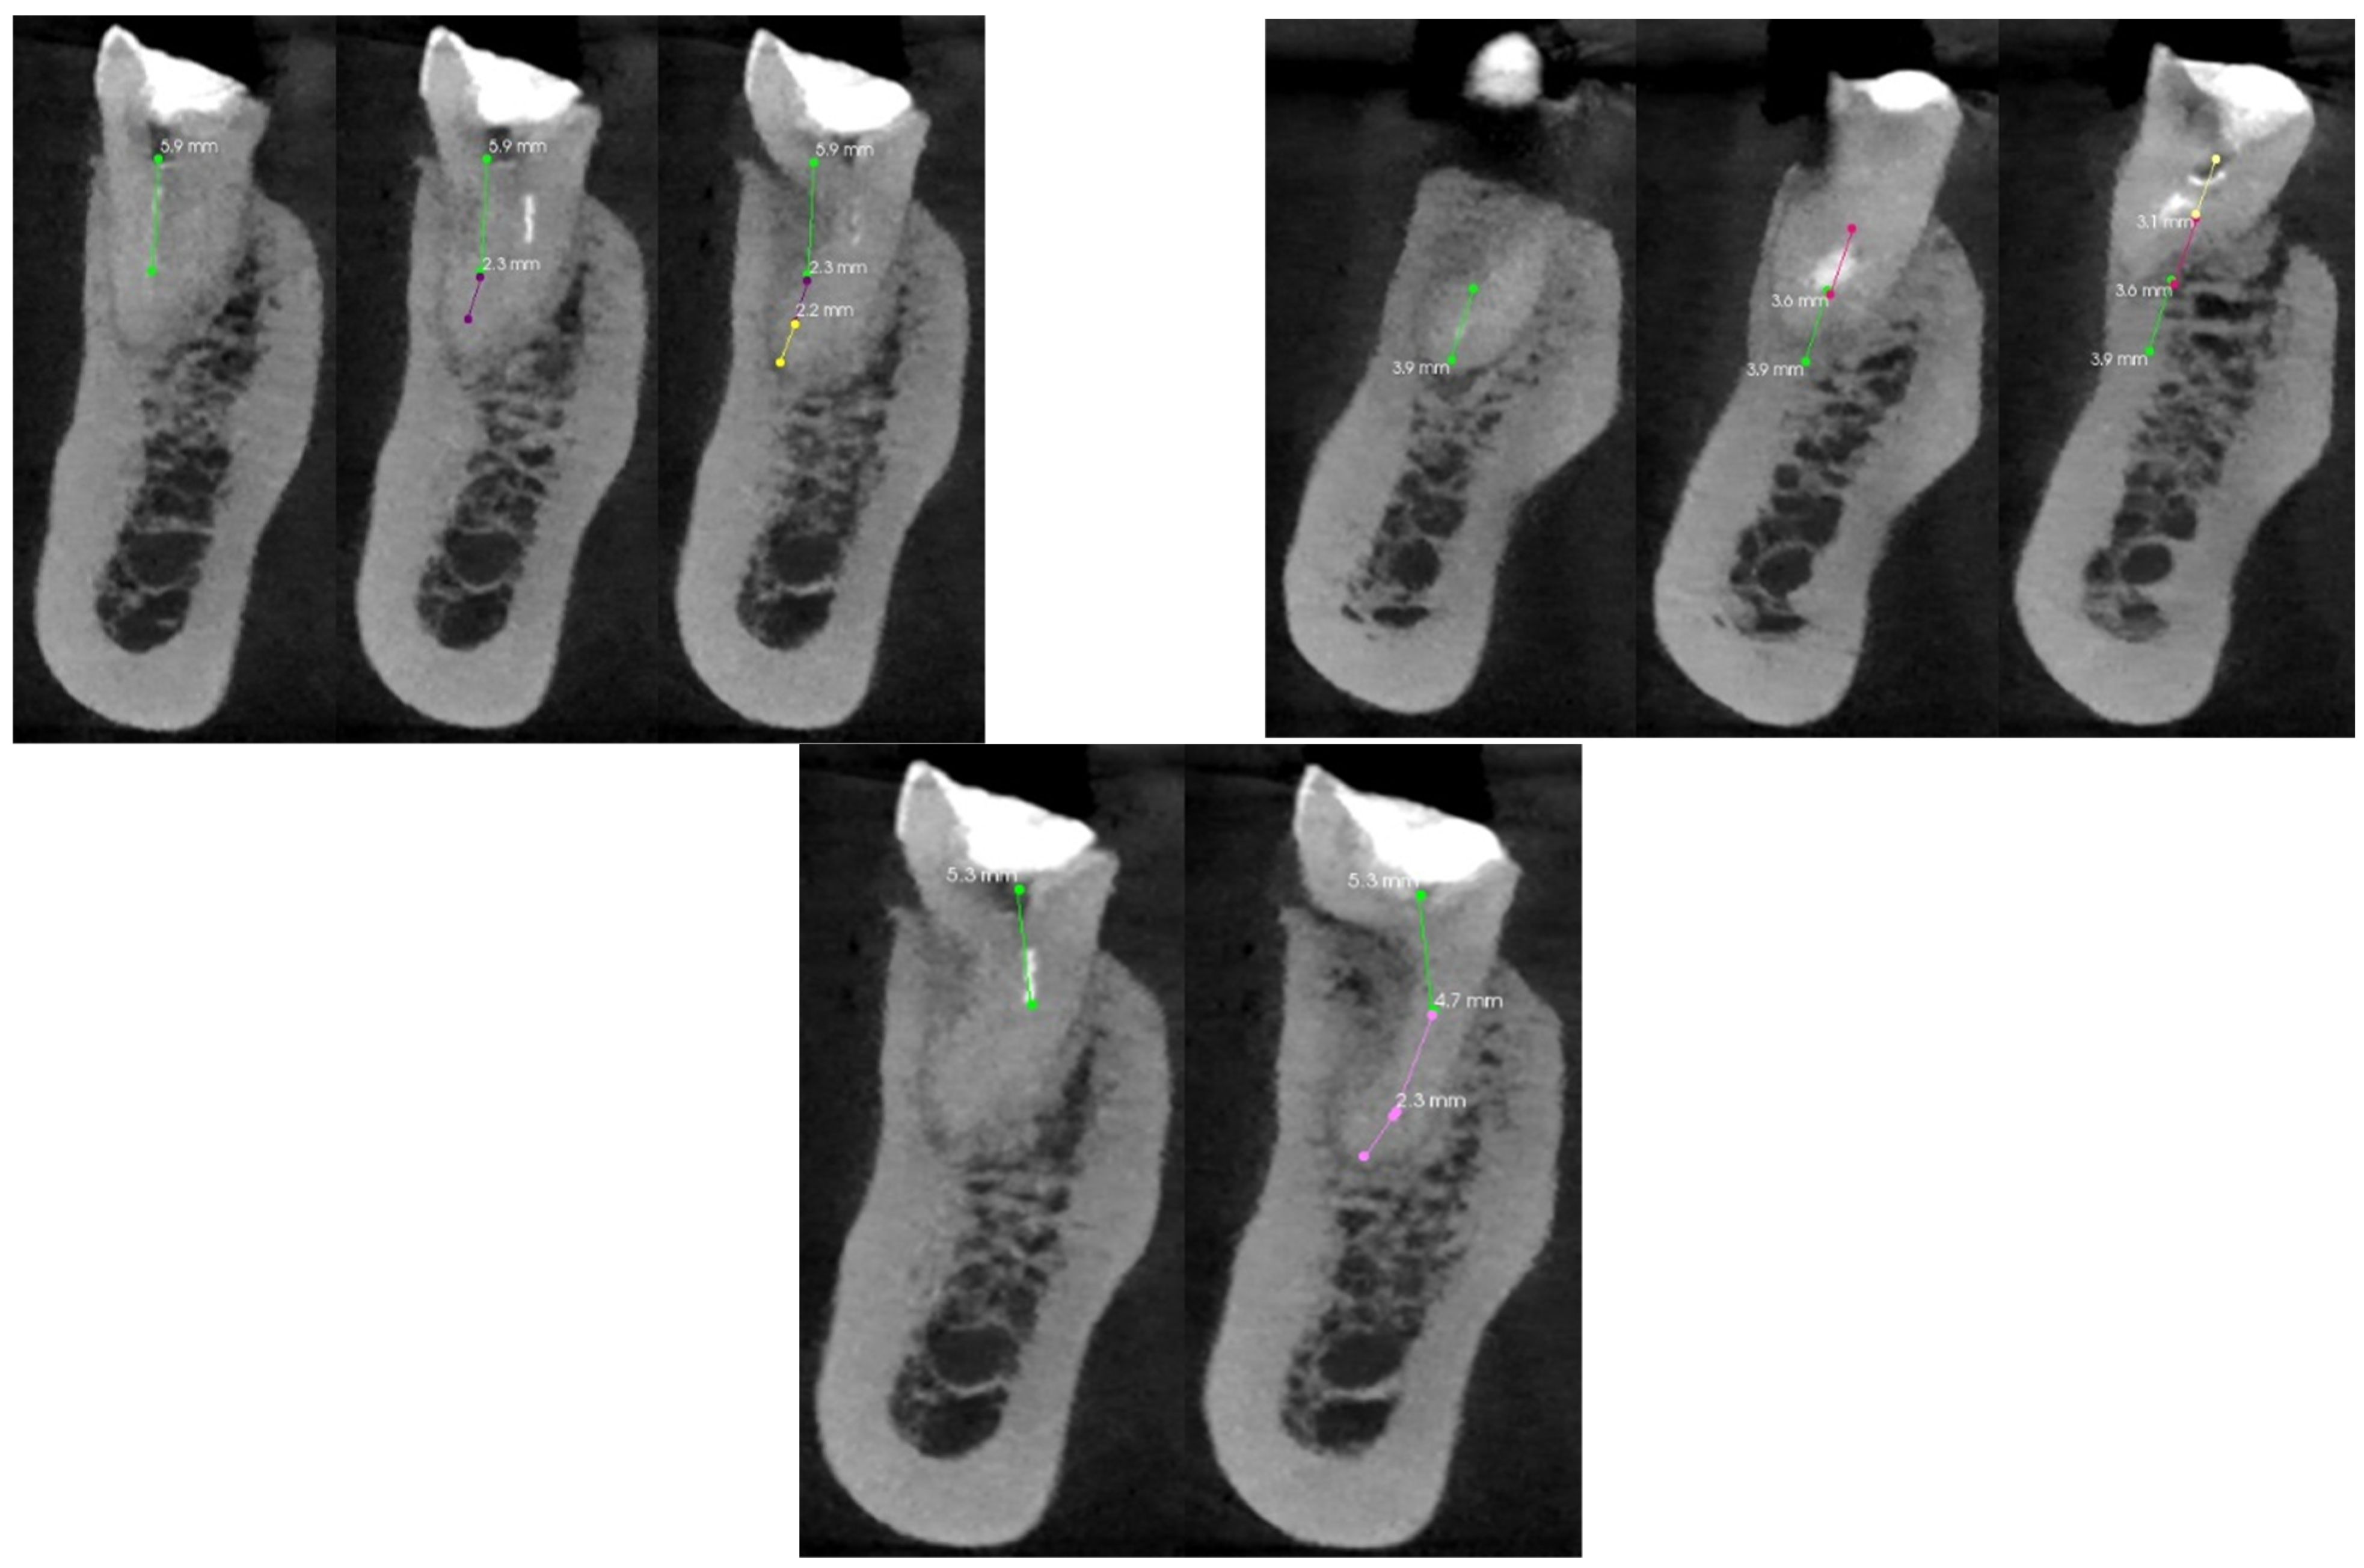

Figure 7 shows the analysis of the root canals in the transverse plane. Each image was analyzed separately. The colored lines indicate the canals visible on the scan. The plane was slowly moved with mouse clicks to show the subsequent sections of the canals, which were then marked with different colors. Each of the canals required the summation of at least two values to approximate the entire length of the root canal. The most complicated turned out to be the distal palatal canal, which required summing up the individual lengths from five scans. Table 2 presents the minimum number of scans for each root canal needed to analyze its entire course and shows the percentage of the length of the canal visible on the scan.

Figure 7. The CT scan of the tooth was used for the analysis of the root canals in the transverse plane, in the case of tooth 17 with carious pulp exposure.